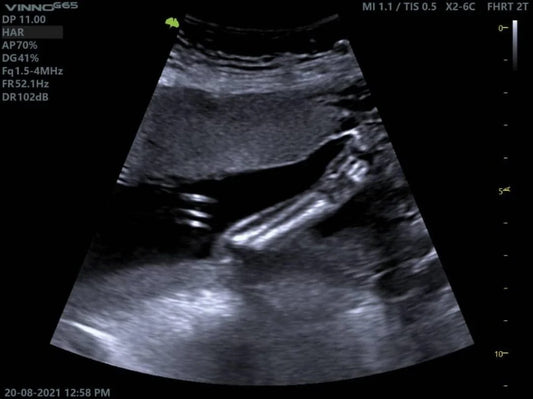

Exploración Abdominal con Ultrasonido: Un Vista...

El ultrasonido abdominal es una herramienta clave para evaluar el tracto digestivo, ofreciendo imágenes en tiempo real y sin recurrir a métodos invasivos ni radiación. Equipos como el VINNO G65...